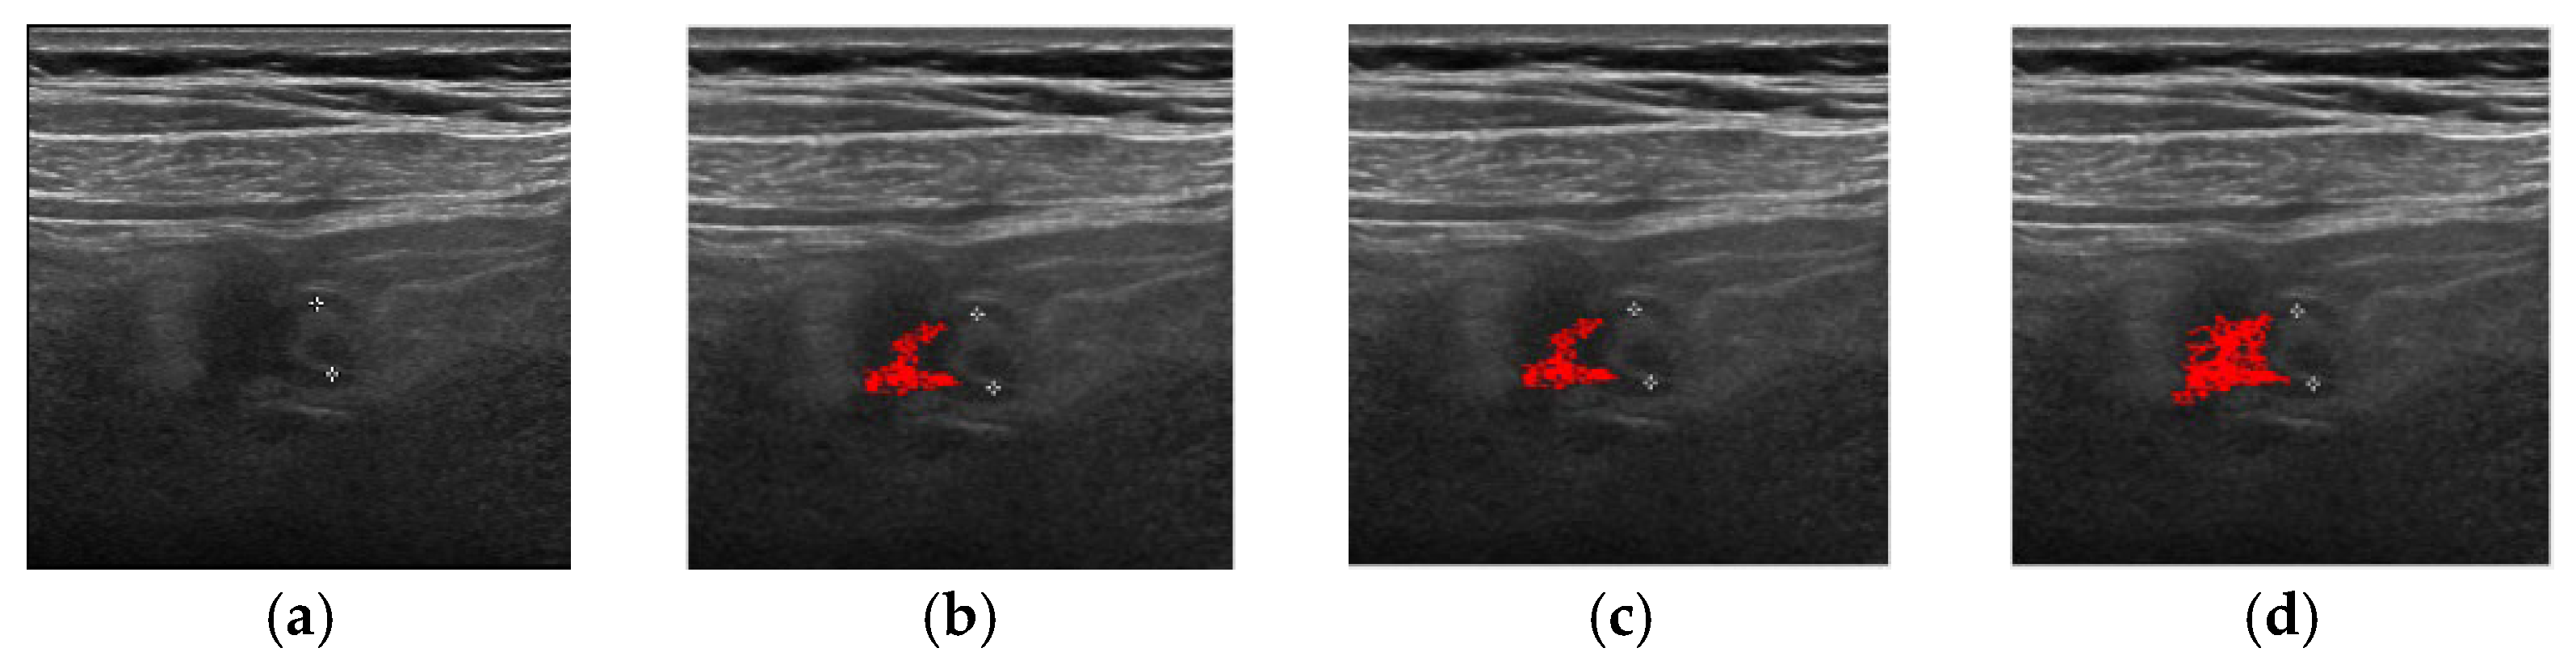

| Method | Successful Images/Total Images |

|---|---|

| FCM | 83/100 |

| ORFCM | 88/100 |

| DFCM | 91/100 |

| DORFCM | 98/100 |

| Accuracy | Precision | Recall | |

|---|---|---|---|

| DORFCM | 84.82% | 83.78% | 86.04% |

| ORFCM | 81.23% | 78.56% | 80.53% |